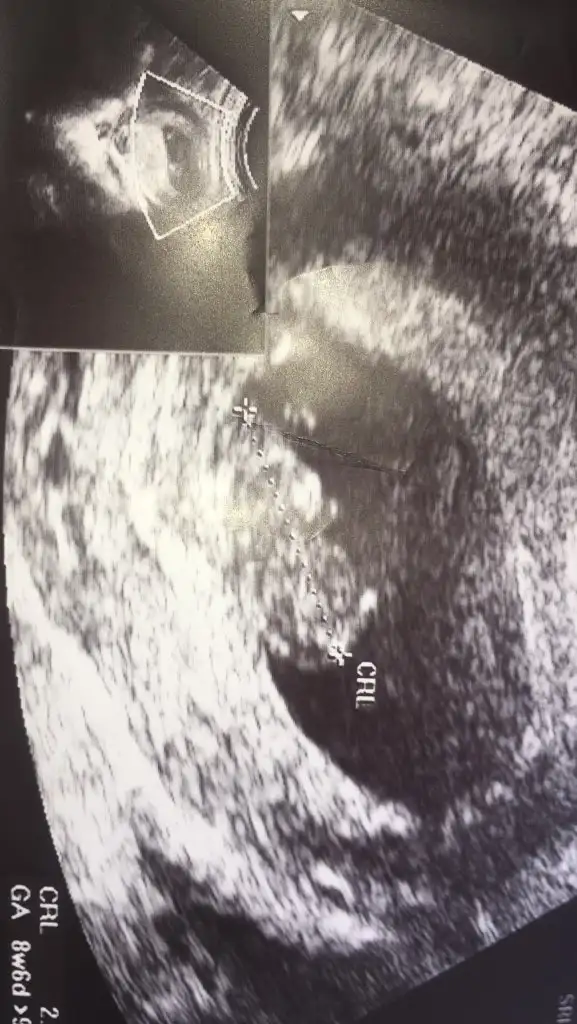

T Takitoki Benim bebeğim 8 haftalık vanija dan bakıldı sağda bebeğim cinsiyeti nedir

Eklentiler

• IMG_20210215_192449.webp

18,7 KB · Görüntüleme: 140